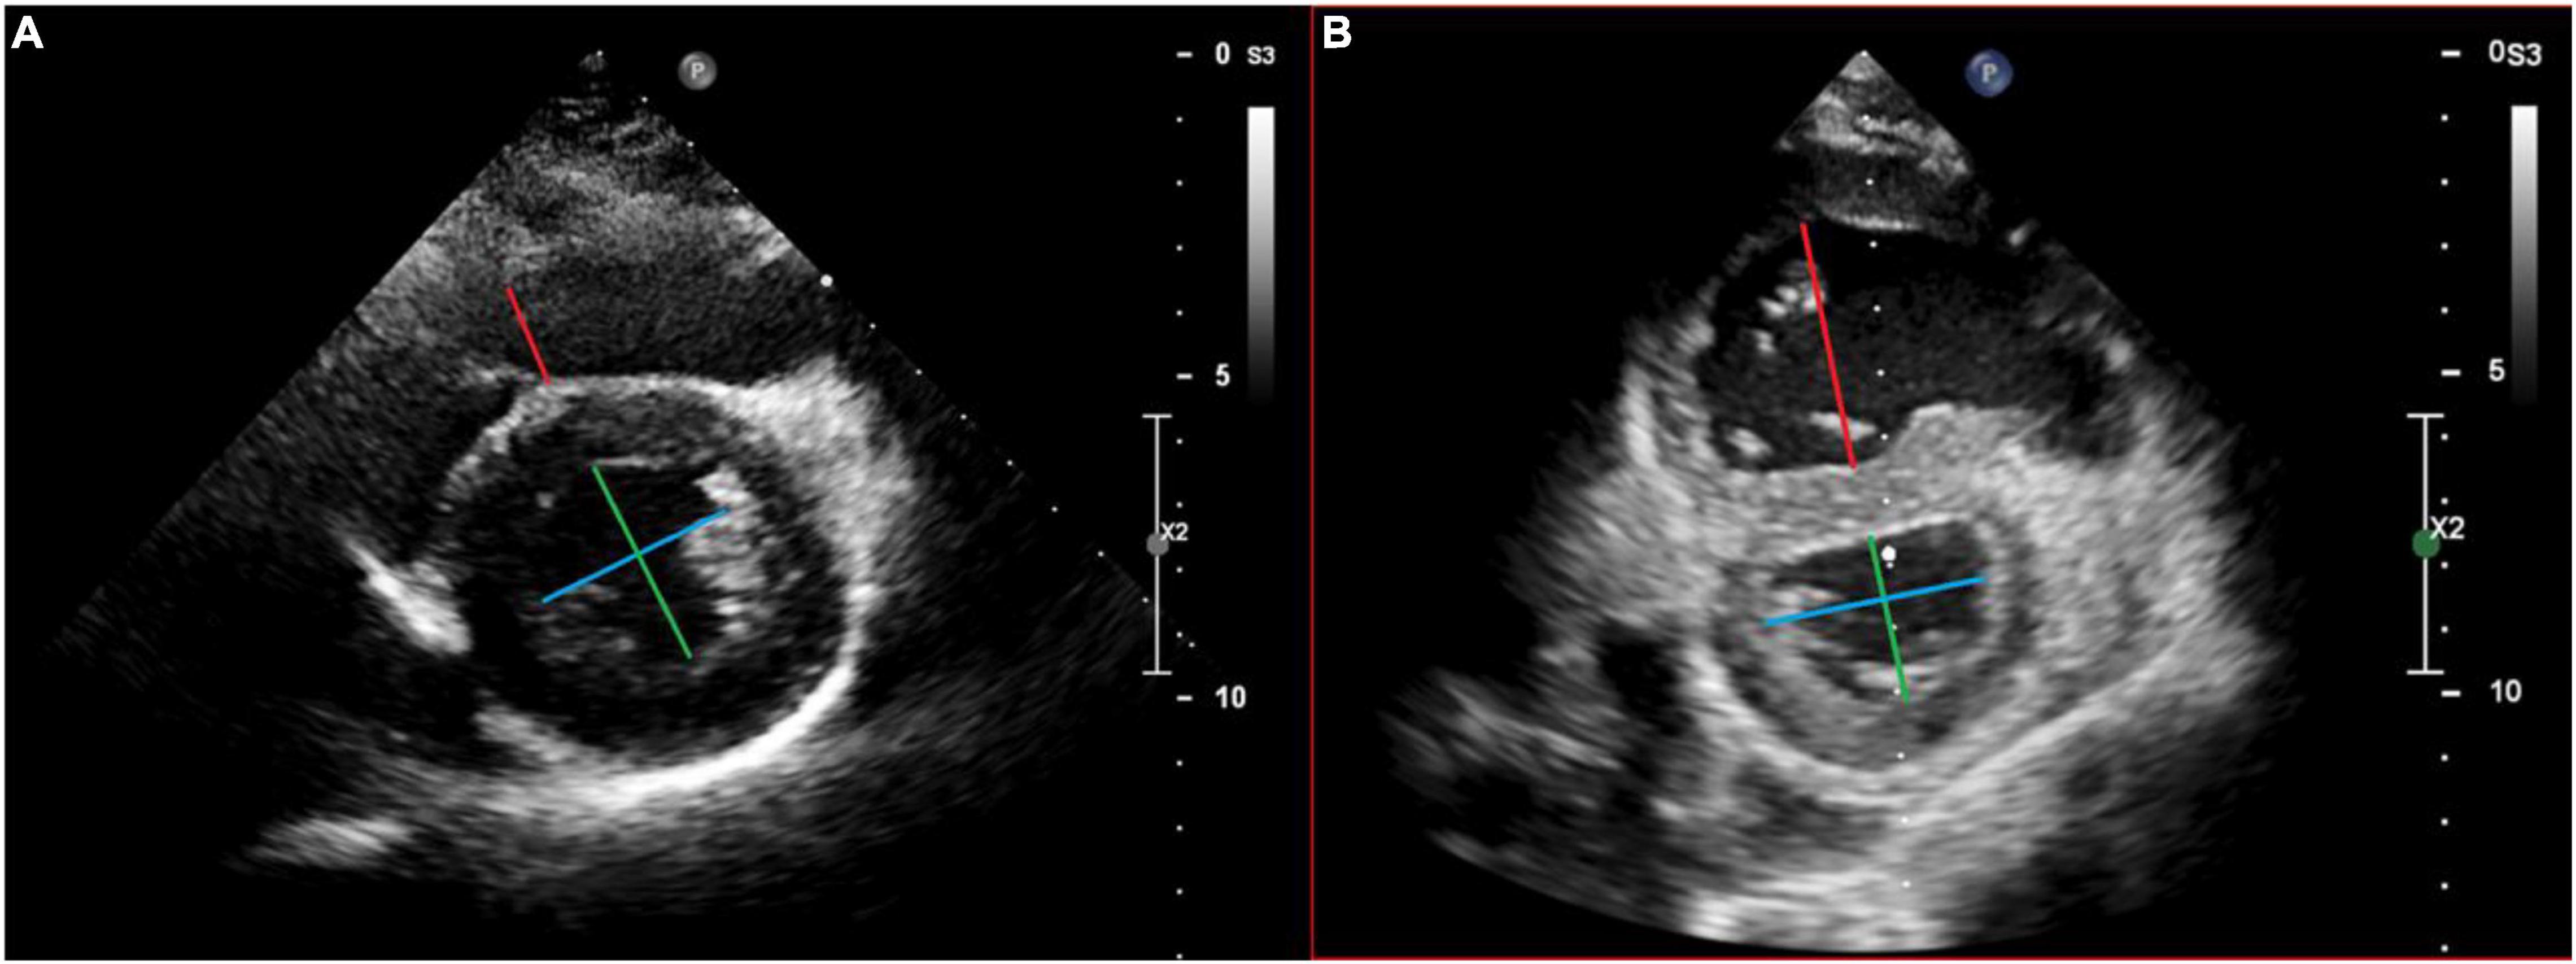

Nonapical Right Ventricular Pacing Is Associated with Less Tricuspid Valve Interference and Long-Term Progress of Tricuspid Regurgitation - ScienceDirect

Frontiers Normal Echocardiographic Reference Values of the Right Ventricular to Left Ventricular Endsystolic Diameter Ratio and the Left Ventricular Endsystolic Eccentricity Index in Healthy Children and in Children With Pulmonary Hypertension

The short term influence of right ventricular pacing burden on echocardiographic and spiroergometric parameters in patients with preserved left ventricular ejection fraction, BMC Cardiovascular Disorders